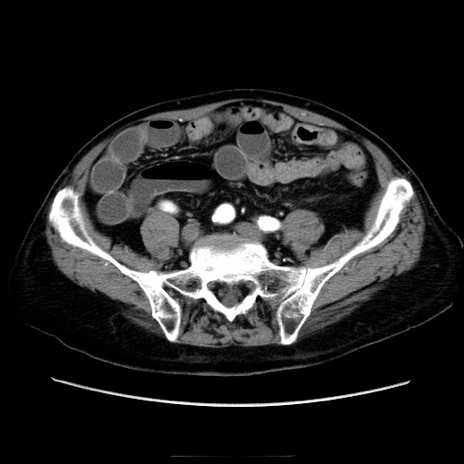

症例21(横断像)

【症例】70歳代男性

【主訴】腹痛

【現病歴】肝硬変・肝細胞癌にてかかりつけの方。約9時間前に食後より腹痛出現。症状が徐々に増悪し、嘔吐出現したため来院。

【既往歴】肝硬変、肝細胞癌(RFA、TACE後)

【身体所見】意識清明、表情苦悶様、BT 36℃、BP 129/78mmHg、P 88bpm、SpO2 97%(RA)、右上腹部から心窩部にかけて圧痛あり、反跳痛なし、筋性防御あり。

【データ】WBC 5800、CRP 0.16